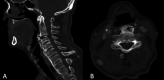

Anterior cervical osteophytosis is a noninflammatory condition characterized by calcification or ossification of the anterolateral paravertebral ligaments of the cervical spine. It affects 20 to 30% of the elderly, being responsible for 1.6% of the identifiable etiologies of dysphagia in the senile population. In advanced states, dysphagia due to cervical osteophytosis can lead to complications such as malnutrition, weight loss and aspiration pneumonia. This study aims to alert to this diagnosis, enabling early treatment of the condition. The case of a 66-year-old male patient with choking dysphagia for solids and nasal food reflux for 1 year is reported. Fiberoptic Endoscopic Evaluation of Swallowing showed bulging of the posterior pharyngeal wall and, with solid food supply, restriction to the retroflexion of the epiglottis, nasal reflux of the food and a large amount of food residue on the lesion. Cervical spine Computed Tomography identified the presence of anterior cervical osteophytes between the C3 and C6 vertebrae, the largest with anteroposterior length of 12 millimeters, narrowing the air column at the level of the oro- and hypopharynx. The patient was adequately treated with swallowing therapy by speech-language pathologist. The initial treatment strategy for symptomatic osteophytosis should be conservative, usually with a good response to swallowing therapy. Although they are rarely implicated in the etiology of dysphagia, considering its high prevalence, it is important that otolaryngologists and speech-language pathologists are attentive to this diagnosis, allowing early and effective treatment for the assisted patient, better prognosis and fewer complications of oropharyngeal dysphagia in the elderly.